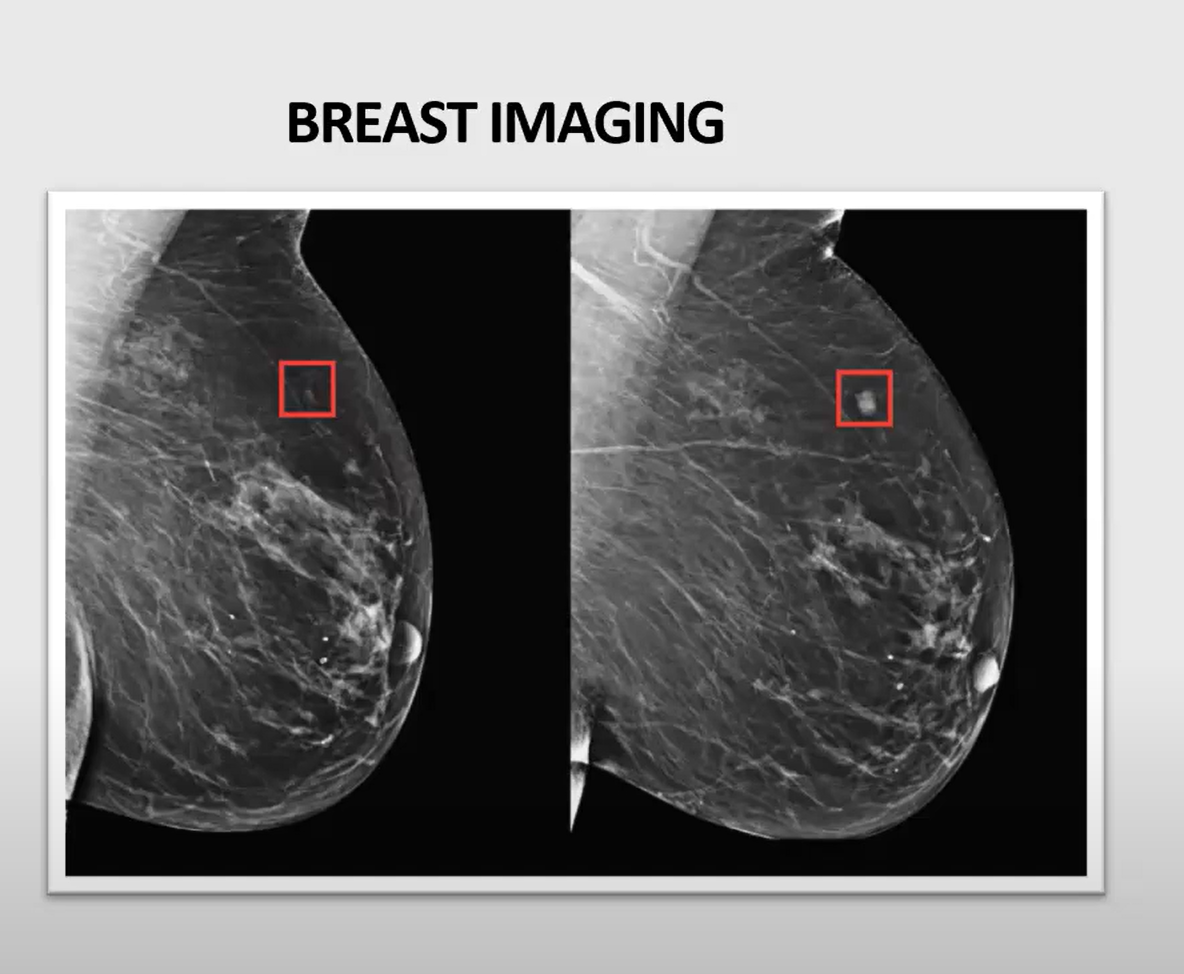

Nekatere radiološke subspecialnosti že hitro uvajajo UI. Foto: zajem zaslona predstavitev iz predstavitve dr. Izroka Cagliča

Foto: zajem zaslona predstavitev iz predstavitve dr. Izroka Cagliča

Klinične uporabe po subspecialnostih

Nekatere radiološke subspecialnosti že hitro uvajajo UI: